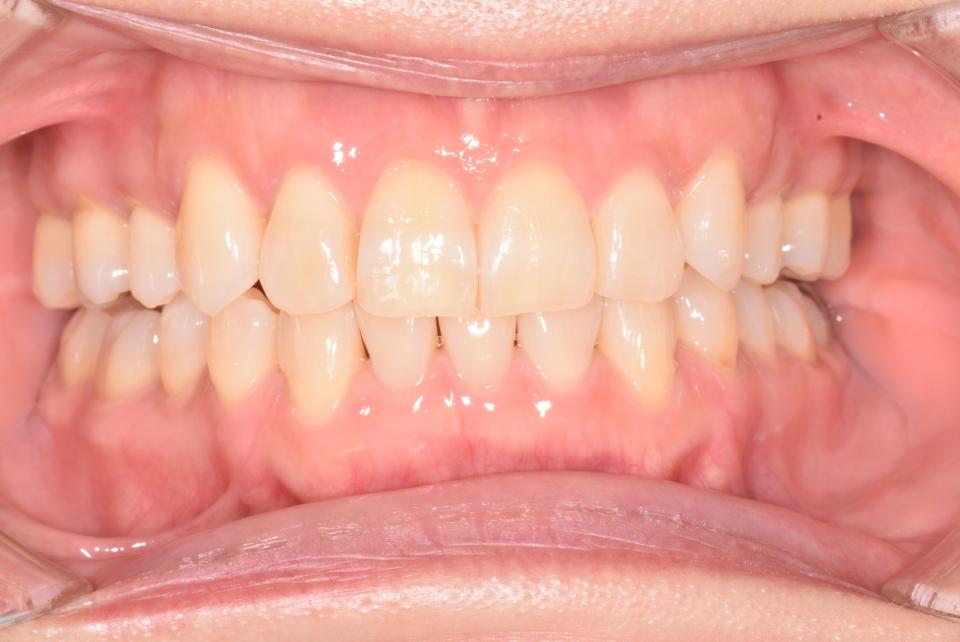

矯正治療後

上の左右4番目の抜歯をして、マウスピース型の矯正治療装置を使用し、歯のやすり掛け(IPR)を行いました。

現在はマウスピース型のリテーナーでで後戻りの防止をして定期的にチェックをしています。

| 矯正治療期間 | 1年10か月 |